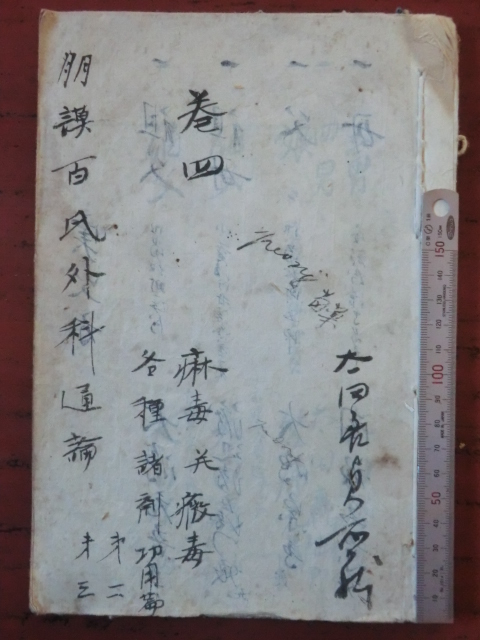

Mechanisms of Nerve Damage in Neuropathies Associated with